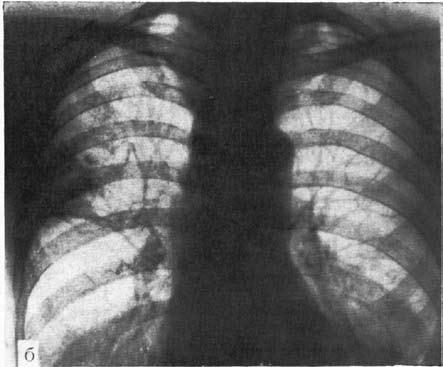

Рис. 18.

Рентгенологическая картина кардиоспазма:

А – при I типе заболевания; Б – при II типе заболевания. (Приводится по: В.Х. Василенко и соавт. Ахалазия кардии. М., 1976)